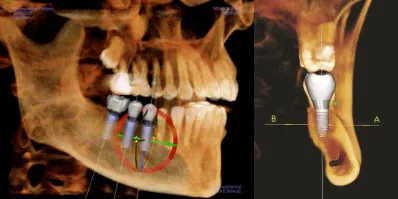

Here at Northwest Valley Oral Maxillofacial and Facial Cosmetic Surgery we are committed to excellence and providing innovative, high quality patient care. Because of this, our practice utilizes the state-of-the-art, full-cranial cone-beam CT (computed tomography) technology that provides highly accurate 3-D radiographic images.

Drs. Hammond or Haralson has direct access to advanced 3-D treatment tools for implants , restorations, oral and maxillofacial surgery, jaw reconstruction, and maxillary sinuses.

i-CAT produces high-definition 3-D diagnostic images for the ultimate treatment efficiency. Its push-button ease delivers maximum control to accurately capture each patient’s unique anatomy and treatment progress.

From diagnosis, through planning and treatment, to successful case completion, i-CAT’s flexibility allows Drs. Hammond or Haralson to select specifically desired scans and to manage radiation dose control for the greatest benefit to his patient’s.

i-CAT’s high resolution, volumetric images provide complete 3-D views for more thorough analysis of bone structure and tooth orientation. This allows Drs. Hammond or Haralson to collect precise data and measurements such as the concavity of the bone and the bone width and height. In the case of multiple implants, Drs. Hammond or Haralson is able to calculate a much more precise positioning of the implant.

This type of imaging allows us to obtain highly accurate information, in an office setting, that was never before thought to be possible. These 3-D radiographic images can obtain very pertinent information on the entire head and neck region. This allows for better diagnosis, better treatment planning, which in turn leads to better surgery. Undistorted, anatomically correct views of the jaws, teeth and facial bones are easily generated. Three-dimensional images enable a level of anatomical accuracy and patient care not possible with 2-D technologies.

Accurate and predictable treatment planning provides an increased level of confidence and extra margin of safety for our patients. We can achieve amazing results with 3-D treatment planning. This allows for the ideal placement of implants while taking into account both clinical and esthetical considerations. The CT guided surgery often allows for immediate loading of prefabricated prosthetics (teeth in a day).